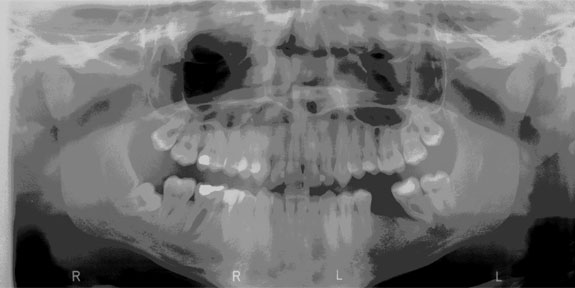

Röntgendiagnosztika